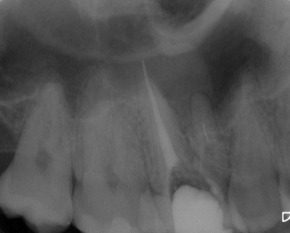

Patient N.M. wünscht eine Drittmeinung, zwischenzeitlich hatte er bereits einen zweiten Zahnarzt konsultiert. Dieser bestätigte eine insuffiziente Wurzelfüllung und vermutete eine Instrumentenfraktur im mb1 (Abb. 1).

Abb. 1: Ausgangsröntgenbild des insuffizient gefüllten Zahnes 16.

Röntgenbefund

Mittels Röntgenaufnahme lässt sich ein frakturiertes Instrument in mb1 vermuten. Des Weiteren scheint es, als sei der distale Wurzelkanal sowie der mb2 nicht abgefüllt worden, was sich zu einem späteren Zeitpunkt der Behandlung bestätigen sollte. Der Patient wurde vom vorbehandelnden Zahnarzt über die Fraktur nicht aufgeklärt.